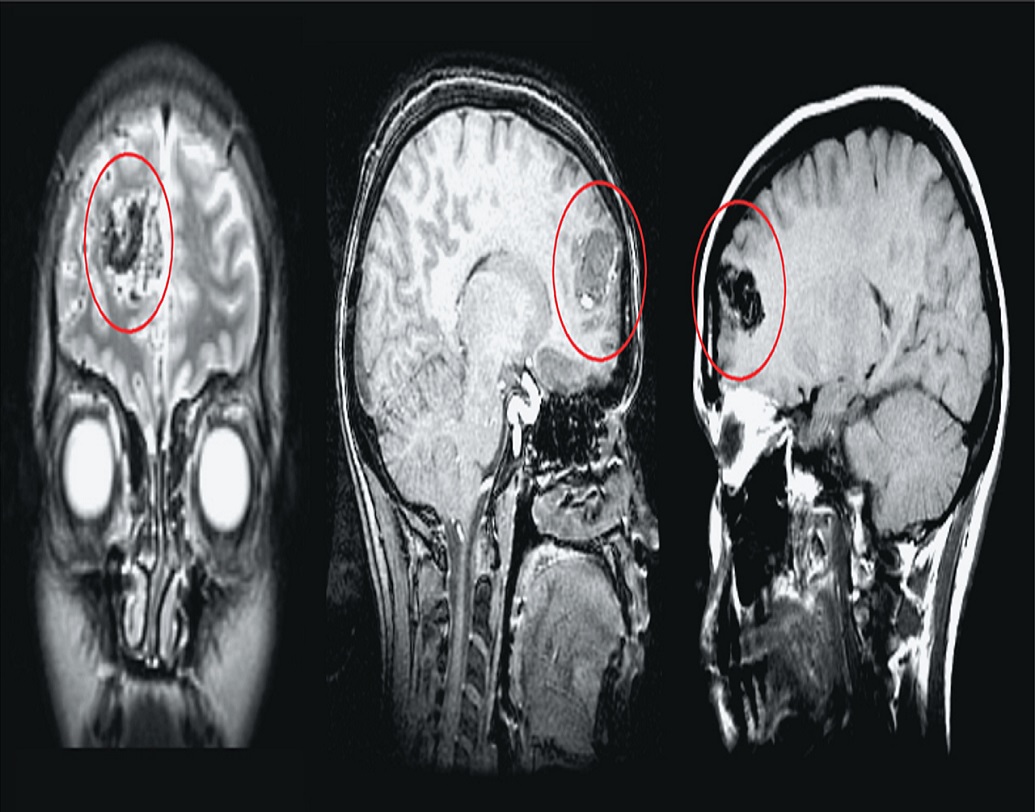

গ্রামবাসীদের ব্রেনের স্ক্যান করে দেখা যায়, তাঁদের মস্তিষ্কে রয়েছে অতিরিক্ত তরল পদার্থ। চিকিৎসার পরিভাষায় যাকে ‘ইডিমা’ বলে। যদিও ওই ইডিমা-র সঠিক কারণ এখনও জানা যায়নি। গ্রামবাসীদের সন্দেহ, তাঁদের এই ঘুমের পিছনে রয়েছে অদূরের ক্রাসনোগোরস্কি ইউরেনিয়াম খনির বাতাস।